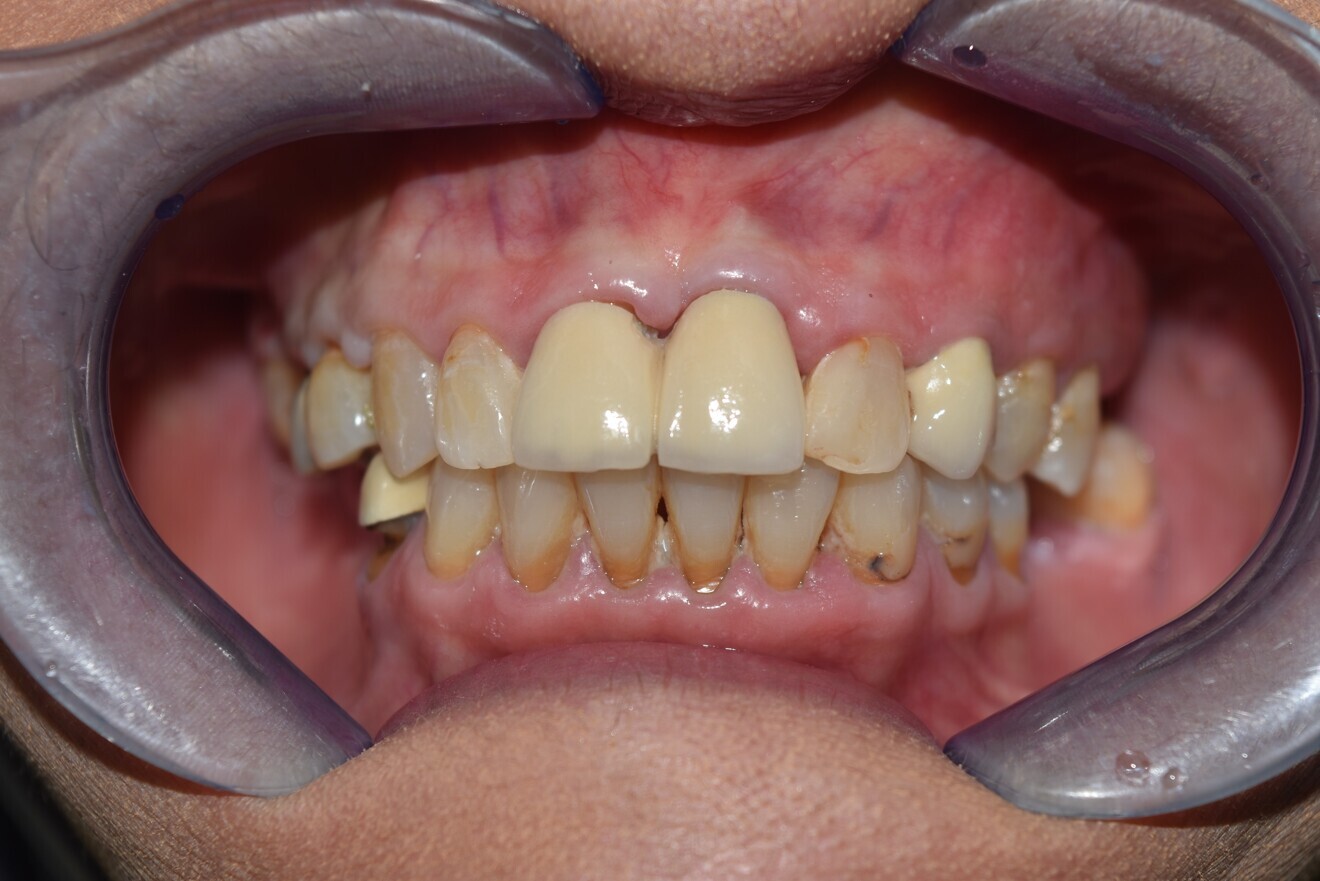

Intra-oral findings:

Class I malocclusion with poli diastemas in both upper and lower arch.

Overbite= 1mm Overjet = 3mm

No molar classification (absence of molars)

Class I canine on right and left side.

Upper midline (mesial to 11) on with face.

Lower midline on with the chin.